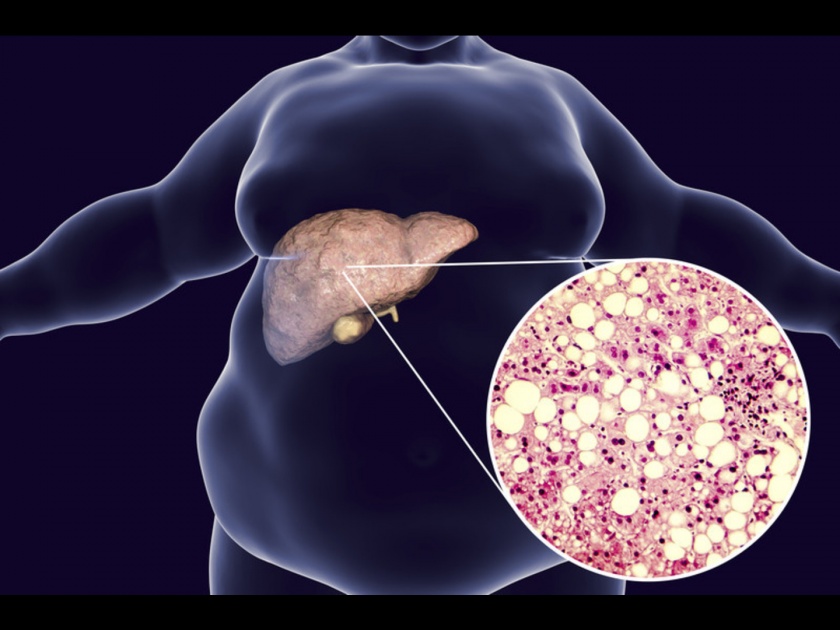

Fatty Liver Remedies: फॅटी लिव्हर आजार झाल्यावर लिव्हरमध्ये जास्त प्रमाणात फॅट जमा होऊ लागतं. लिव्हरमध्ये फॅट जमा होण्याची अनेक कारणे आहेत. ही समस्या फार जास्त प्रमाणात मद्यसेवन केल्यानेही होते आणि अनहेल्दी लाइफस्टाईलमुळेही होते. फॅटी लिव्हर आजार झाल्यावर याचे सुरूवातीचे संकेत ओळखणं फार अवघड असतं. पण जर तुम्हाला जास्त थकवा, वजन कमी होणे सोबत पोटदुखीची समस्या झाली असेल तर वेळीच डॉक्टरांना दाखवा.

फॅटी लिव्हरचा धोका - जर तुम्हाला फॅटी लिव्हर समस्येपासून सुटका मिळवायची असेल तर आधी तुम्हाला रिस्क फॅक्टर्सबाबत जाणून घेणं गरजेचं आहे. लठ्ठपणा, स्लीप एपनिया, ट्राइग्लिसराइड्सचं प्रमाण हाय, हायपोथायरॉडिज्म आणि डायबिटीसमुळे फॅटी लिव्हरची समस्या जास्त वाढू लागते. अनेकदा काही औषधांमुळेही लिव्हरमध्ये फॅट जमा होऊ लागतं.